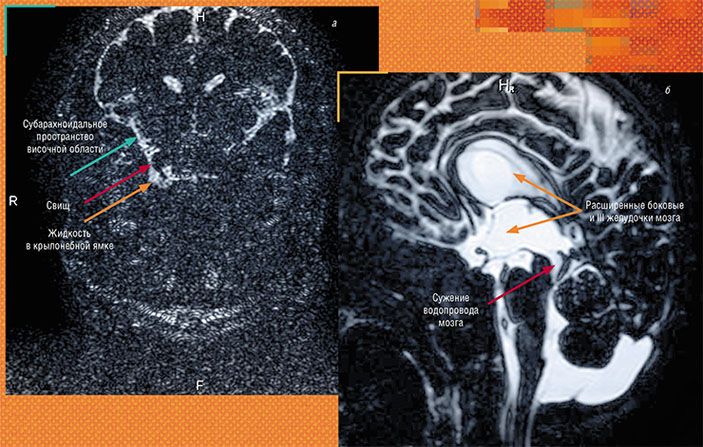

Тонкосрезовые трехмерные МРТ-методики позволяют определить наличие стойких сужений тонких ликворных структур, патологических отверстий-фистул и нетипичных путей оттока спинномозговой жидкости: слева — свищ, дефект твердой мозговой оболочки, представляющий патологическое соединение (канал) между ликворным пространством височной области и крылонебной ямкой — щелевидным пространством черепа, в котором в норме ликвора нет. Ямка сообщается с носовой полостью, поэтому в случае свища ликвор начинает вытекать через нос; справа — выраженное воронковидное сужение дистальных отделов водопровода мозга у ребенка с вентрикуломегалией (увеличением желудочков)